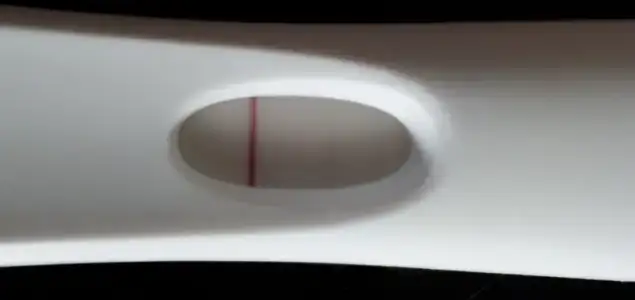

insallah canim benim hic hissim yok canim hala yok. Bende surekli bakiyordum belirtisi olmayip hamile olanlari